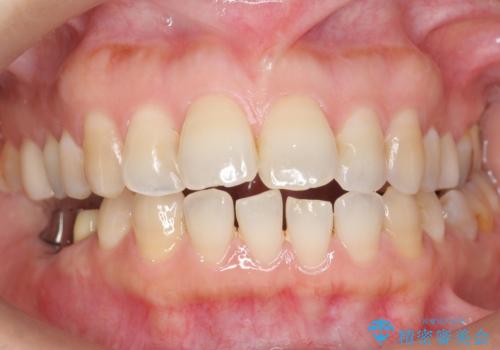

奥歯でしっかり噛むことができるようになり、喜んで頂けました。

セラミッククラウンの審美的な仕上がりにもご満足頂けました。

クラウンの種類:ベレッツァクラウン(右下76)、ジルコニアクラウン スタンダード(右下5)